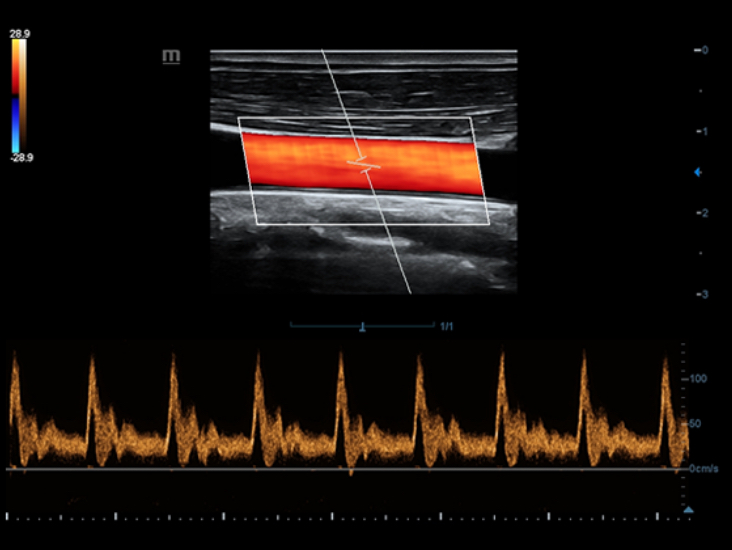

Специализированный уход благодаря ECHO

Совместно с современными ультразвуковыми технологиями новое решение от Mindray преобразует актуальные задачи клиентов в клинические потребности. Постоянно развиваясь, эта система сочетает в себе стремление к неограниченным возможностям и желание заглянуть в будущее.

Многофункциональная система DC-60 Exp с X-Insight представляет собой комплексное решение, которое помогает управлять повседневной клинической практикой с легкостью и уверенностью.

Основываясь на глубоком понимании потребностей клиентов, компания Mindray разработала систему DC-60 Exp с X-Insight, чтобы обеспечить высокую производительность и точность визуализации вкупе с наглядностью, исключительной интеллектуальностью и огромным опытом.